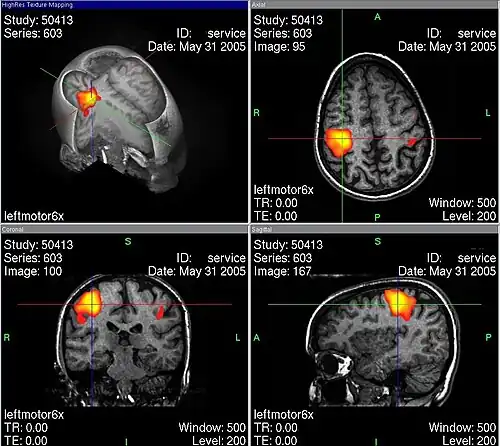

Gehirnareale mit gesteigerter neuronaler Aktivität werden stärker durchblutet.[10] Die Mechanismen dieses als reaktive Hyperämie oder neurovaskuläre Kopplung bezeichneten Phänomens beinhalten die Reaktion der Widerstandsgefäße auf den lokalen Kohlendioxidpartialdruck, weitere vasoaktive Faktoren und die neurogene Steuerung des Vasotonus,[11] sind im Einzelnen aber noch nicht völlig geklärt.

Funktionelle MRT – stärker durchblutete Areale eingefärbt

Funktionelle MRT – stärker durchblutete Areale eingefärbt -